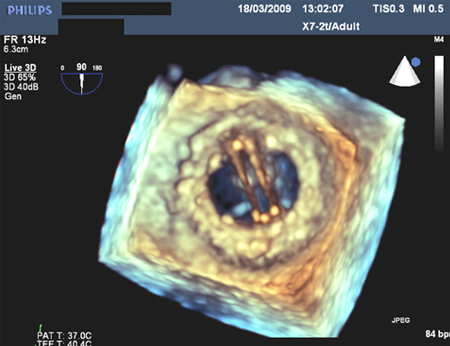

[Figure caption and citation for the preceding image starts]: Prosthetic mitral valve with intermittent mitral regurgitationFrom the collection of Prakash P. Punjabi [Citation ends].

Additionally, three-dimensional transesophageal echocardiogram provides a surgical view of the mitral valve, which can help the heart team discussion on intervention strategy.[10]Otto CM, Nishimura RA, Bonow RO, et al. 2020 ACC/AHA guideline for the management of patients with valvular heart disease: a report of the American College of Cardiology/American Heart Association Joint Committee on Clinical Practice Guidelines. Circulation. 2021 Feb 2;143(5):e72-227.